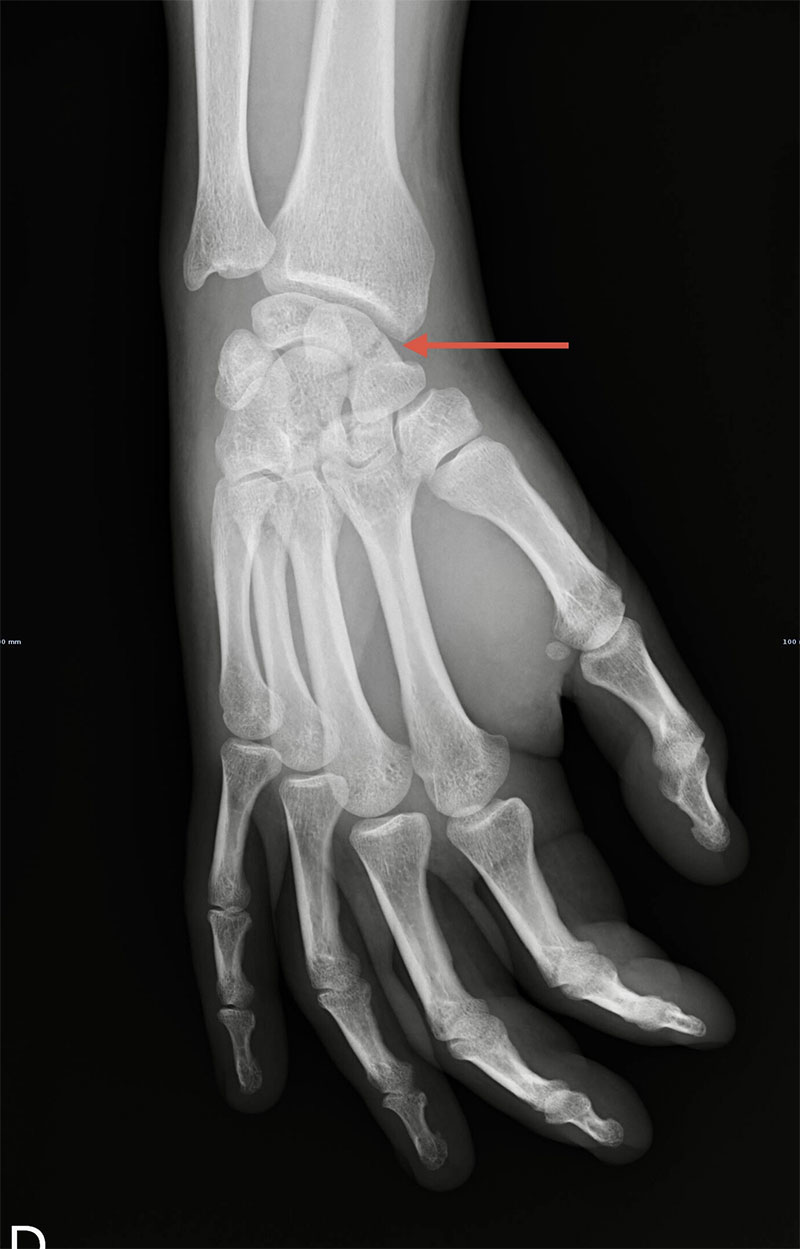

Raio-X demonstrando fractura do 1/3 médio do escafóide